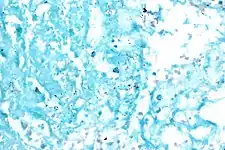

Acid fast bacilli, Ziehl–Neelsen stain.